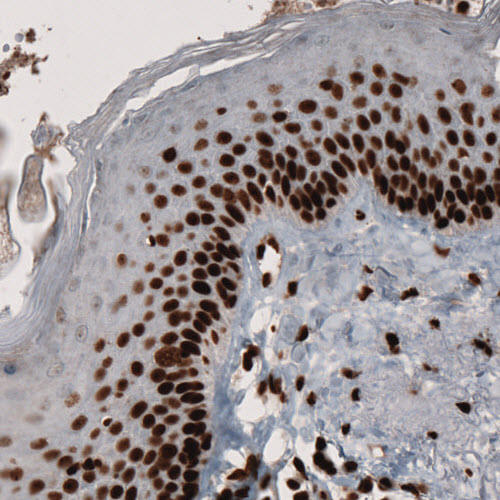

Immunohistochemistry-Paraffin: PARP Antibody [NBP3-44462]

Staining of human kidney shows nuclear positivity in both tubuli and glomeruli.